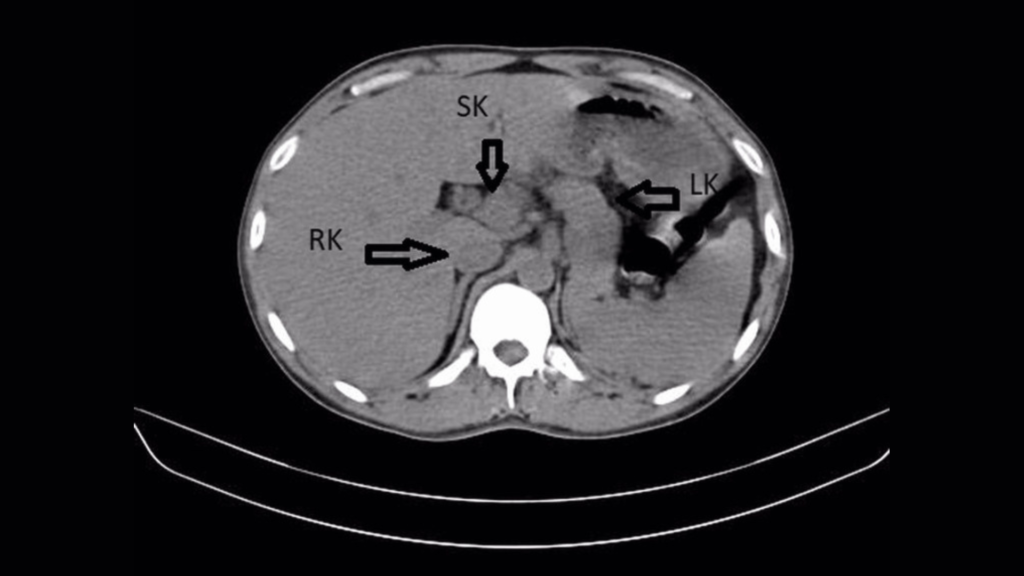

But an additional ultrasound and CT scan of the patient’s abdomen revealed something unexpected. It is the third kidney, also known as the supernumerary kidney. It had fused with the man’s right kidney, forming a horseshoe shape.

In this case, the patient’s left and right kidneys were swollen and showed an accumulation of stones or mineral crystals. These hard crystals form when urine becomes more concentrated. Small “stones” often pass normally when urinating, but if left untreated in the kidney, they can cause an infection.

Signs of infection were more severe in the left kidney, where stones had accumulated in the left ureter, the tube that connects the left kidney to the bladder.